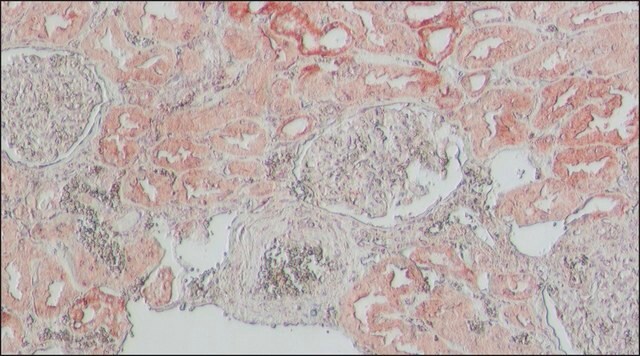

The antibody may be used in various immunochemical techniques including ELISA, Immunoblotting and Immunohistochemistry. Detection of the ACE2 band by Immunoblotting is specifically inhibited by the immunogen.